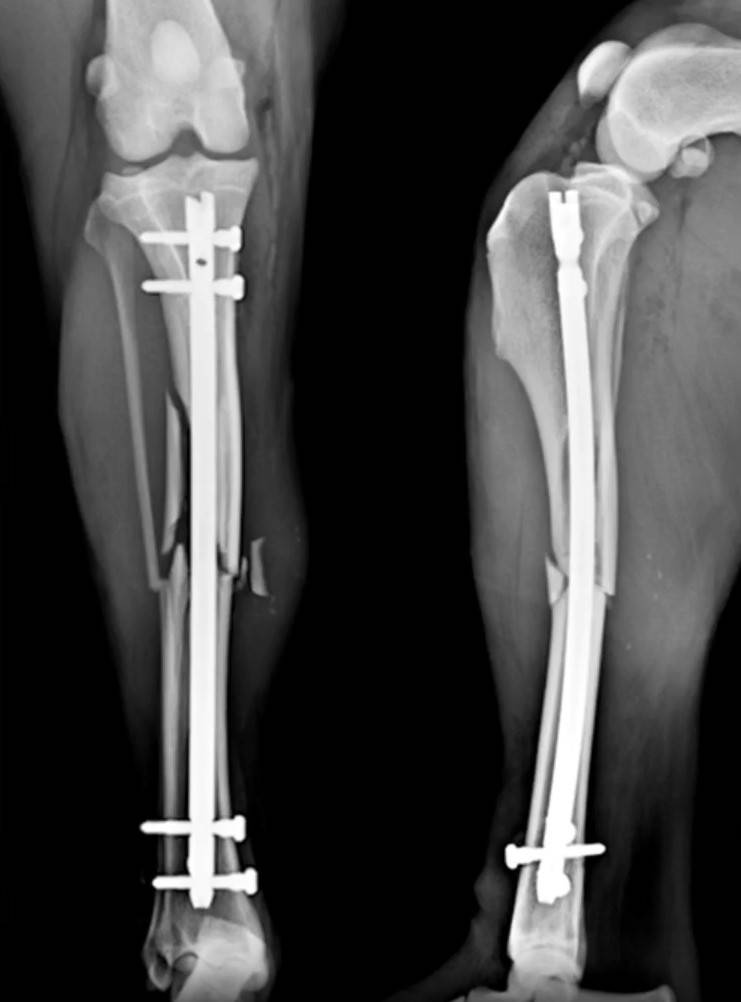

Tibial Plateau Levelling Osteotomy (TPLO) Course

Tibial plateau levelling osteotomies have become popular techniques for the treatment of canine cranial cruciate ligament disease. While the osteotomy is more invasive than some of the other techniques,  there is increasing evidence that it may produce better results than other surgeries long term. We strongly recommend attending a practical course before attempting these techniques.

Securos University has trained many veterinary surgeons worldwide to a level where they feel confident to use what they have learned on the course in their clinical practice. In the morning session we will initially focus on the pathophysiology of cranial cruciate ligament disease, the biomechanics of TPLO and surgical planning of the technique. In addition, there will be a review of a surgery, practice of the procedure on a sawbone, and then round one of performing and assisting on a canine cadaver.

The afternoon will commence with a radiograph critique of the mornings procedure followed by round two of the TPLO procedure. We will conclude the lab with another radiograph review, Q&A and reception.